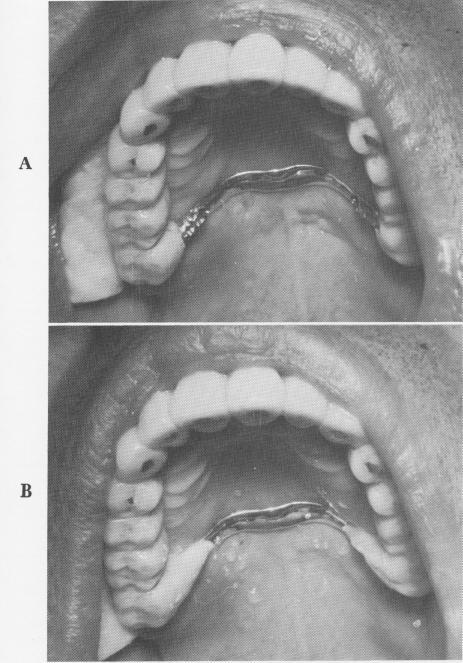

Fig. 4-37. A, The pins were bent flush with palatal bar and B, sealed to it with acrylic.

1 Tripod pin implant through palatal bar in bone to save prosthesis

2 Tripod implant pins bent flush with palatal bar, sealed with acrylic